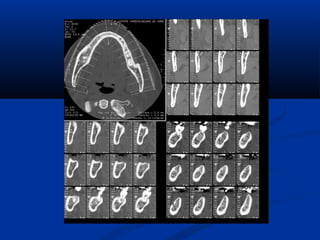

U maùu vuøng haømU maùu vuøng haøm

(T)/(T)/ Daõn tónh maïchDaõn tónh maïch

caûnh ngoaøi (T)caûnh ngoaøi (T)

U maùu vuønghaømU maùu vuøng haøm (T)/(T)/ Daõn tónh maïchDaõn tónh maïch caûnh ngoaøi (T)caûnh ngoaøi (T)